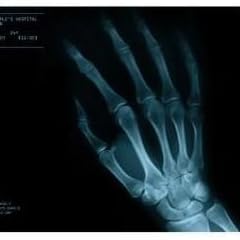

壁使う逆立ちの練習してて

右足の小指やっちゃいました

http://open2ch.net/p/news4vip-1396629359-91.png